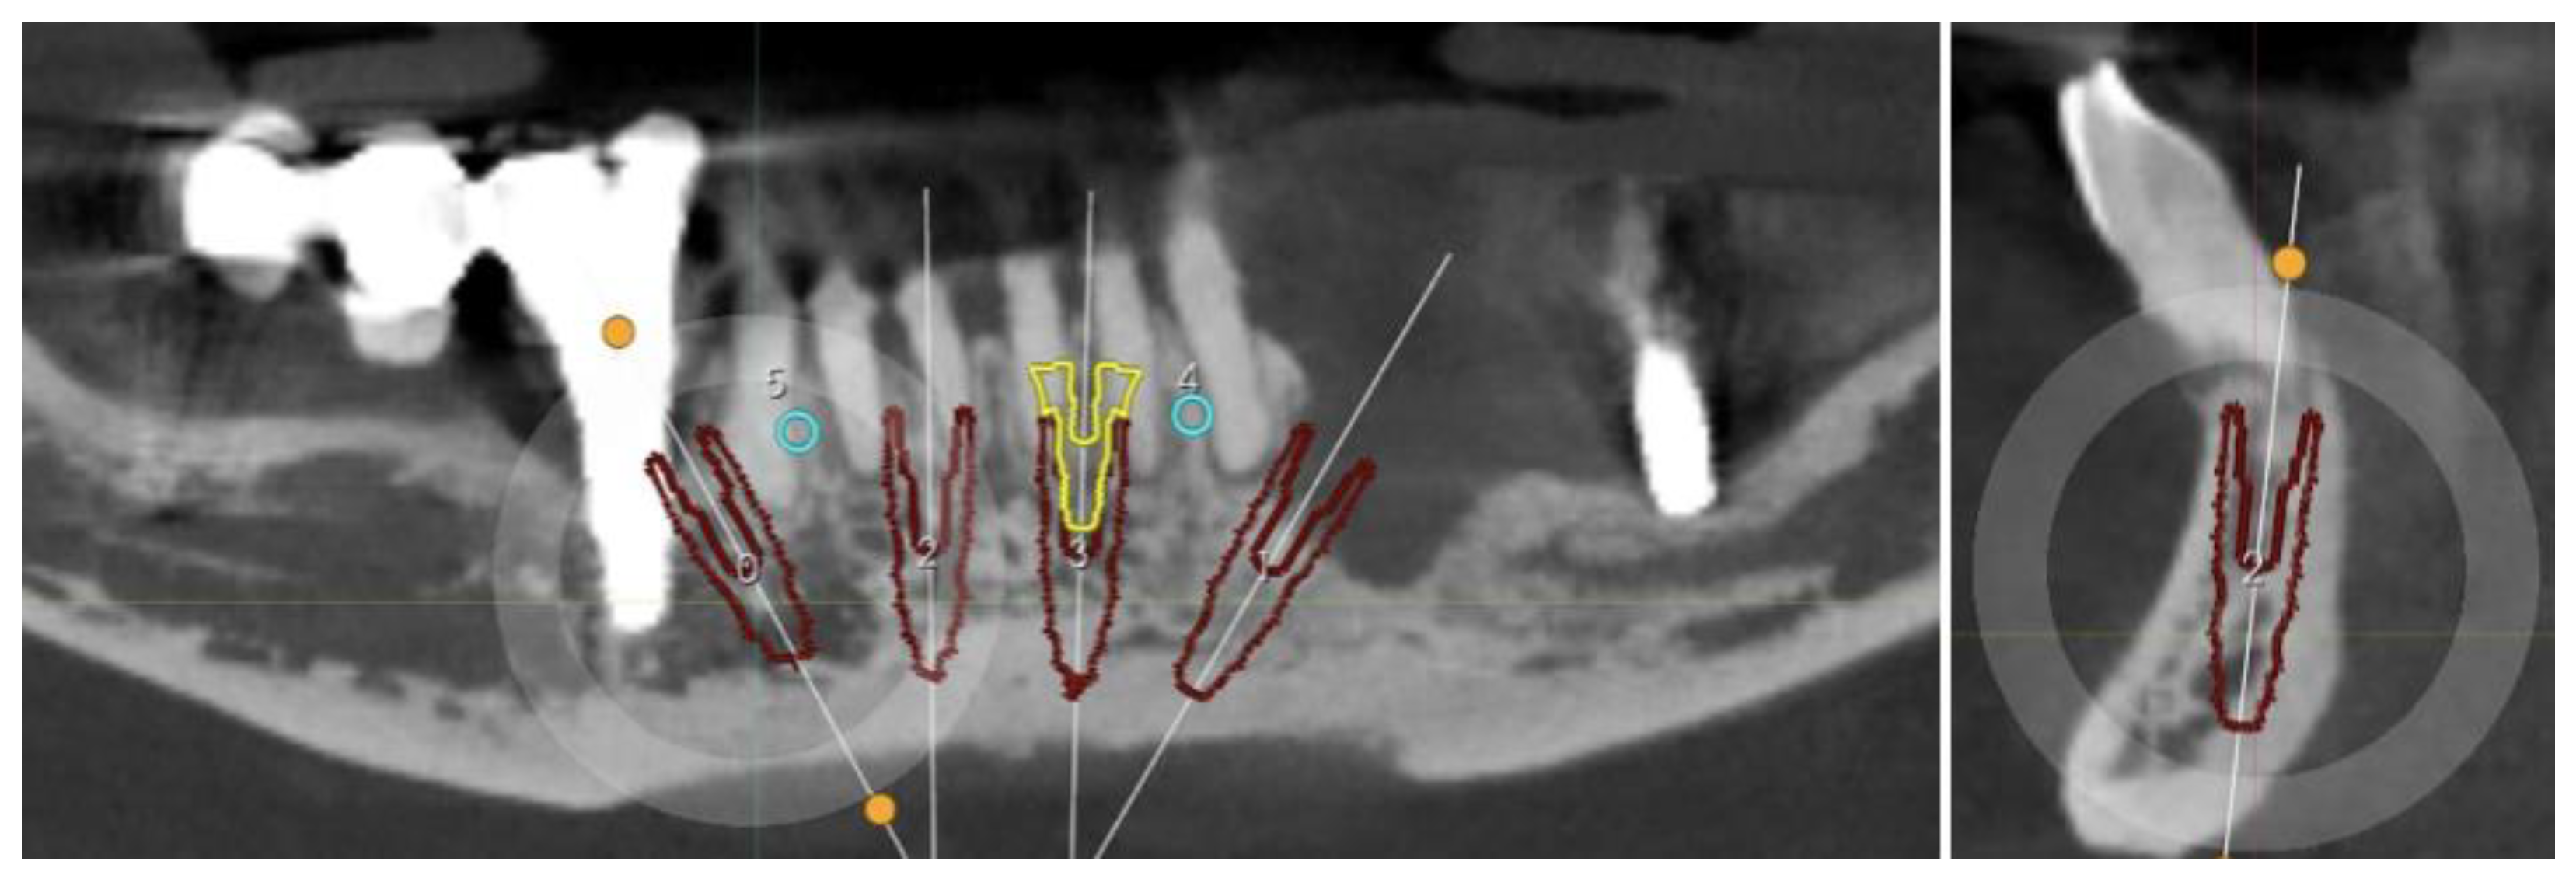

2.1. Planning

Surgical Guide